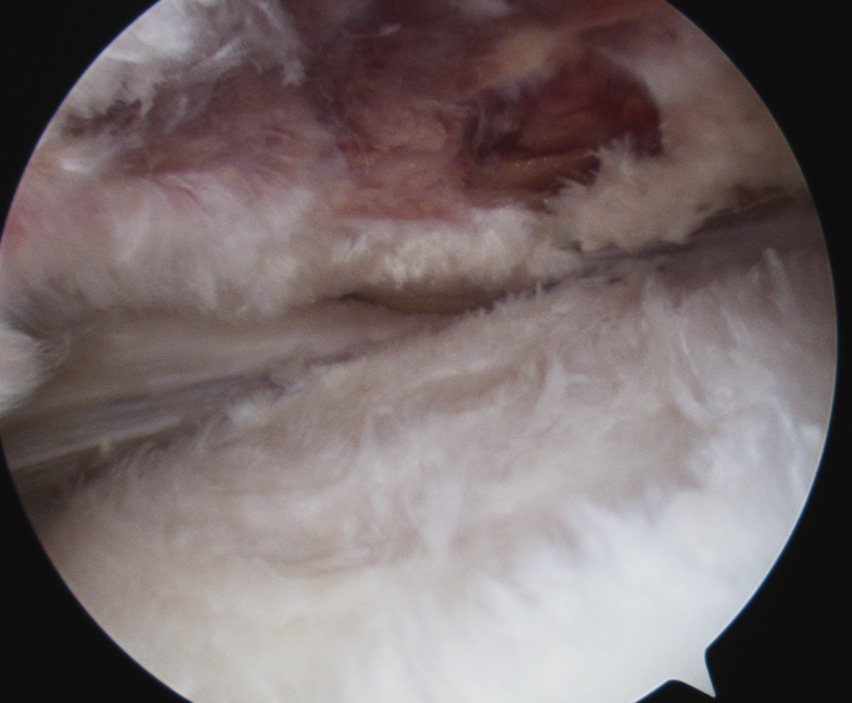

> 50% uncovering of footprint in glenohumeral joint